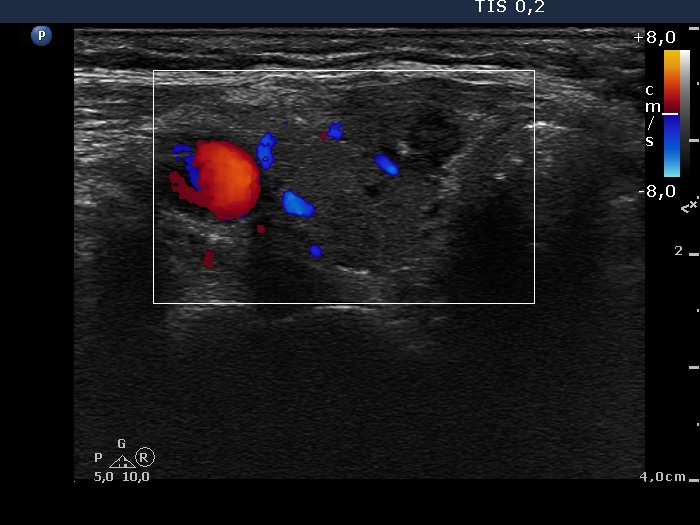

Ultrasonography. There was a hypoechogenic nodule presenting microcalcification in the ventromedial part of the right lobe. Corresponding to the palpable mass in the right submandibular area, a lymph node was found. The node did not present hilum.